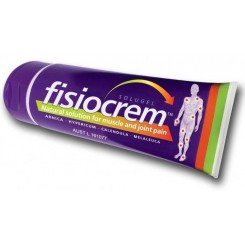

Ortopedia Deportiva

Hay 4 productos.